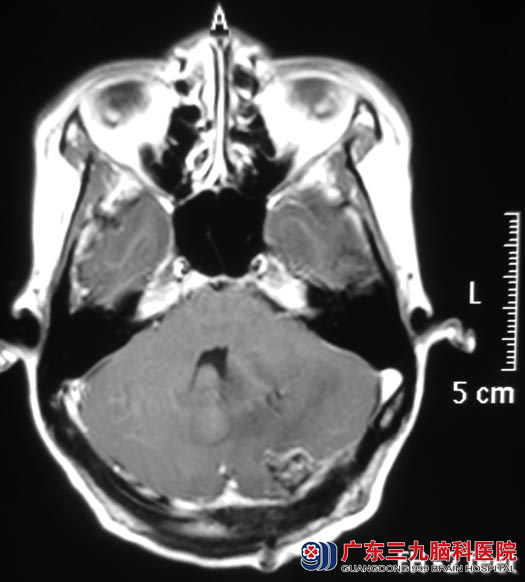

占女士一向身体健康。二个月前开始出现头晕,程度轻,没有头痛、呕吐、走路不稳等症状,间断性发作。为慎重起见,她在家人的陪伴下去医院检查,头颅CT检查提示:左侧小脑低密度病灶,脑组织肿胀。http://www.999brain.com/

广东三九脑科医院头颅MR检查提示:左侧小脑半球囊性病灶,大小约28.3mm×28.3mm×23.5mm。